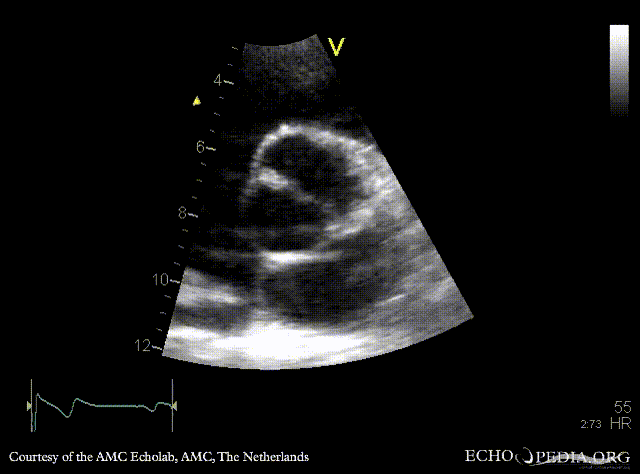

PLAX: dilated ascending aorta in patient with bicuspid aortic valve PSAX: bicuspid aortic valve